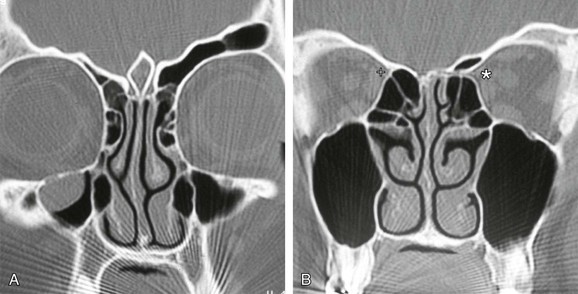

The anterior ethmoid artery can also be damaged during sinus surgery. It is at risk as it passes through the roof of the ethmoid sinuses on its way from the orbit to the anterior cranial fossa.88 Damage to the artery can lead to profuse epistaxis, intraorbital bleeding, and at times intracranial bleeding.89 The development of a retroorbital hemorrhage is an emergency, because it can lead to blindness. The bony canal in which the anterior ethmoid artery crosses the skull base can be dehiscent, making it vulnerable to damage.90 A dehiscence of the anterior ethmoid artery of 11% to 40% has been reported.91 Bony protrusions from the lateral end of the bony canal of the artery are apparent, both where it emerges from the orbit and medially, where it goes through the lateral lamella. Some authors have stated that the artery lies behind the frontal recess and can act as a landmark when approaching this area.92,93 Stammberger90 located the anterior ethmoid artery 1 to 2 mm behind the junction of the posterior wall of the frontal recess and anterior ethmoid air cells. Simmen and colleagues94 showed a mean distance from the posterior wall of the frontal recess to the artery of 11 mm (range 6 to 15 mm). In most cases the position of the artery is mirrored on both sides. However, it is variable and, consequently, it is not safe to use the artery as a landmark for any endoscopic intervention, especially in locating the frontal recess. The anterior ethmoid artery is always seen between the second and third lamella, and the most common site to find the artery is in the suprabullar recess (85%). If pneumatization of the ethmoid is marked, the artery is likely to be lying below the skull base, where it is more prone to surgical damage. Preoperative knowledge of suprabullar recess and supraorbital cells by careful interpretation of CT scans is helpful in avoiding damage to the anterior ethmoid artery (Fig. 42-22).